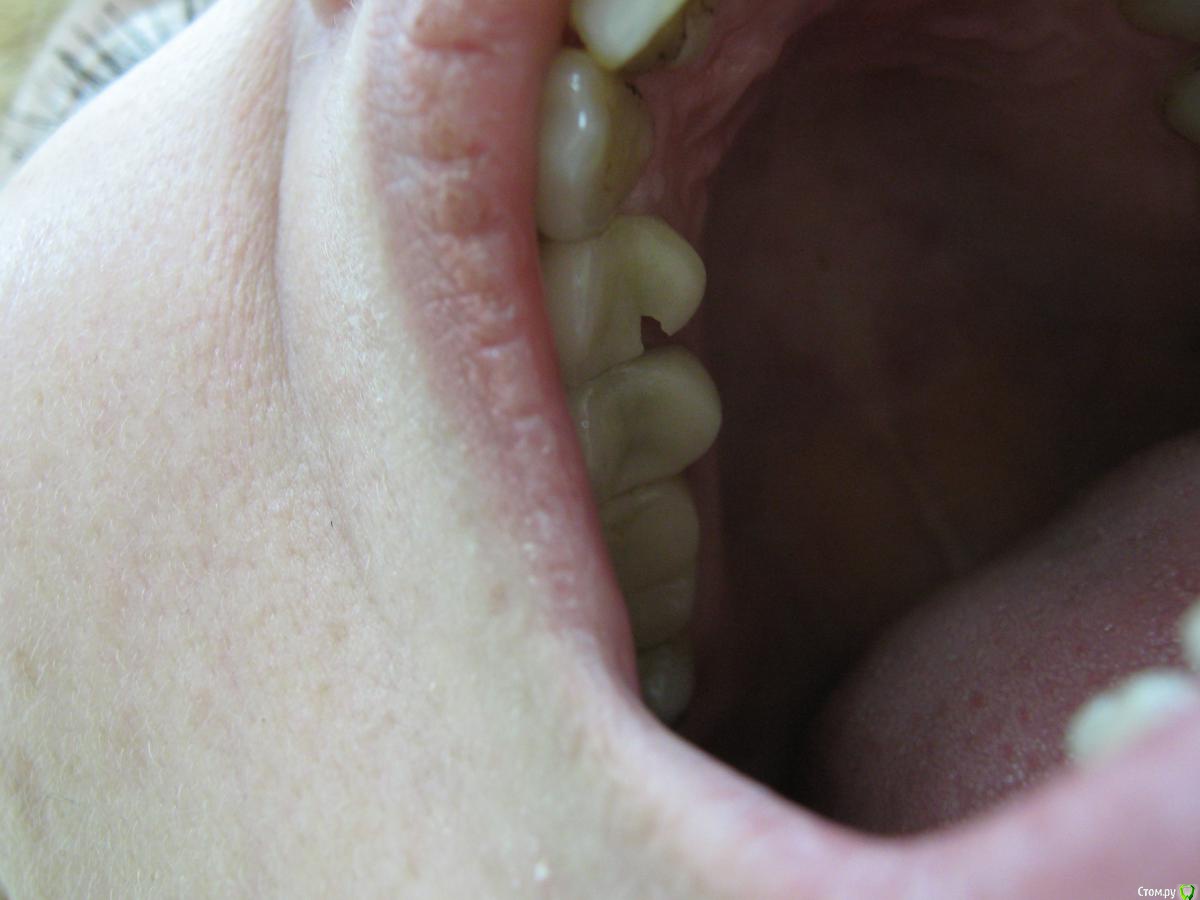

Кирилл 1986 Опубликовано 8 февраля, 2016 Поделиться Опубликовано 8 февраля, 2016 Цельнокерамические коронки на 14,15 зубах (Duceram Kiss на огнеупорной модели), поставлены чуть больше года назад, прилегание коронок сохранено,без изменений, окклюзионная схема тоже. Скол в фиссуре,на всю толщину коронки, произошёл со слов пациента при жевании яблока, скорее всего одним куском ( керамики). При жевании ничего не мешало, зубочистками пациент не пользовался. Какие могут быть причины скола? Что учесть при замене коронки? Ссылка на комментарий